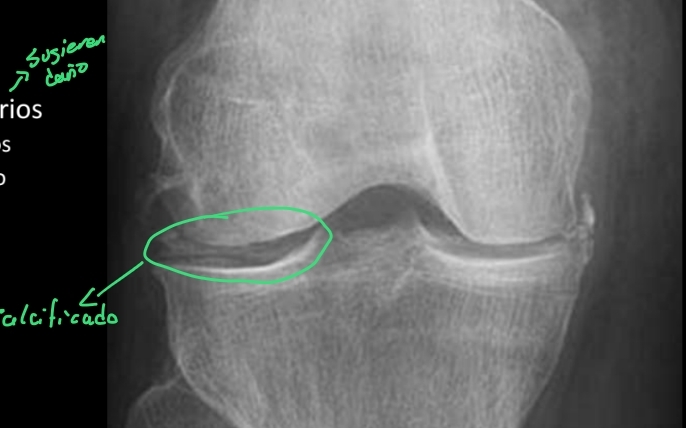

Para qué se usan los Rx en el desgarro meniscal?

A

Se ven datos secundarios que sugieren que hubo un daño

- Edema de tejidos blandos

- Calcificaciones = crónico

No se ce el menisco